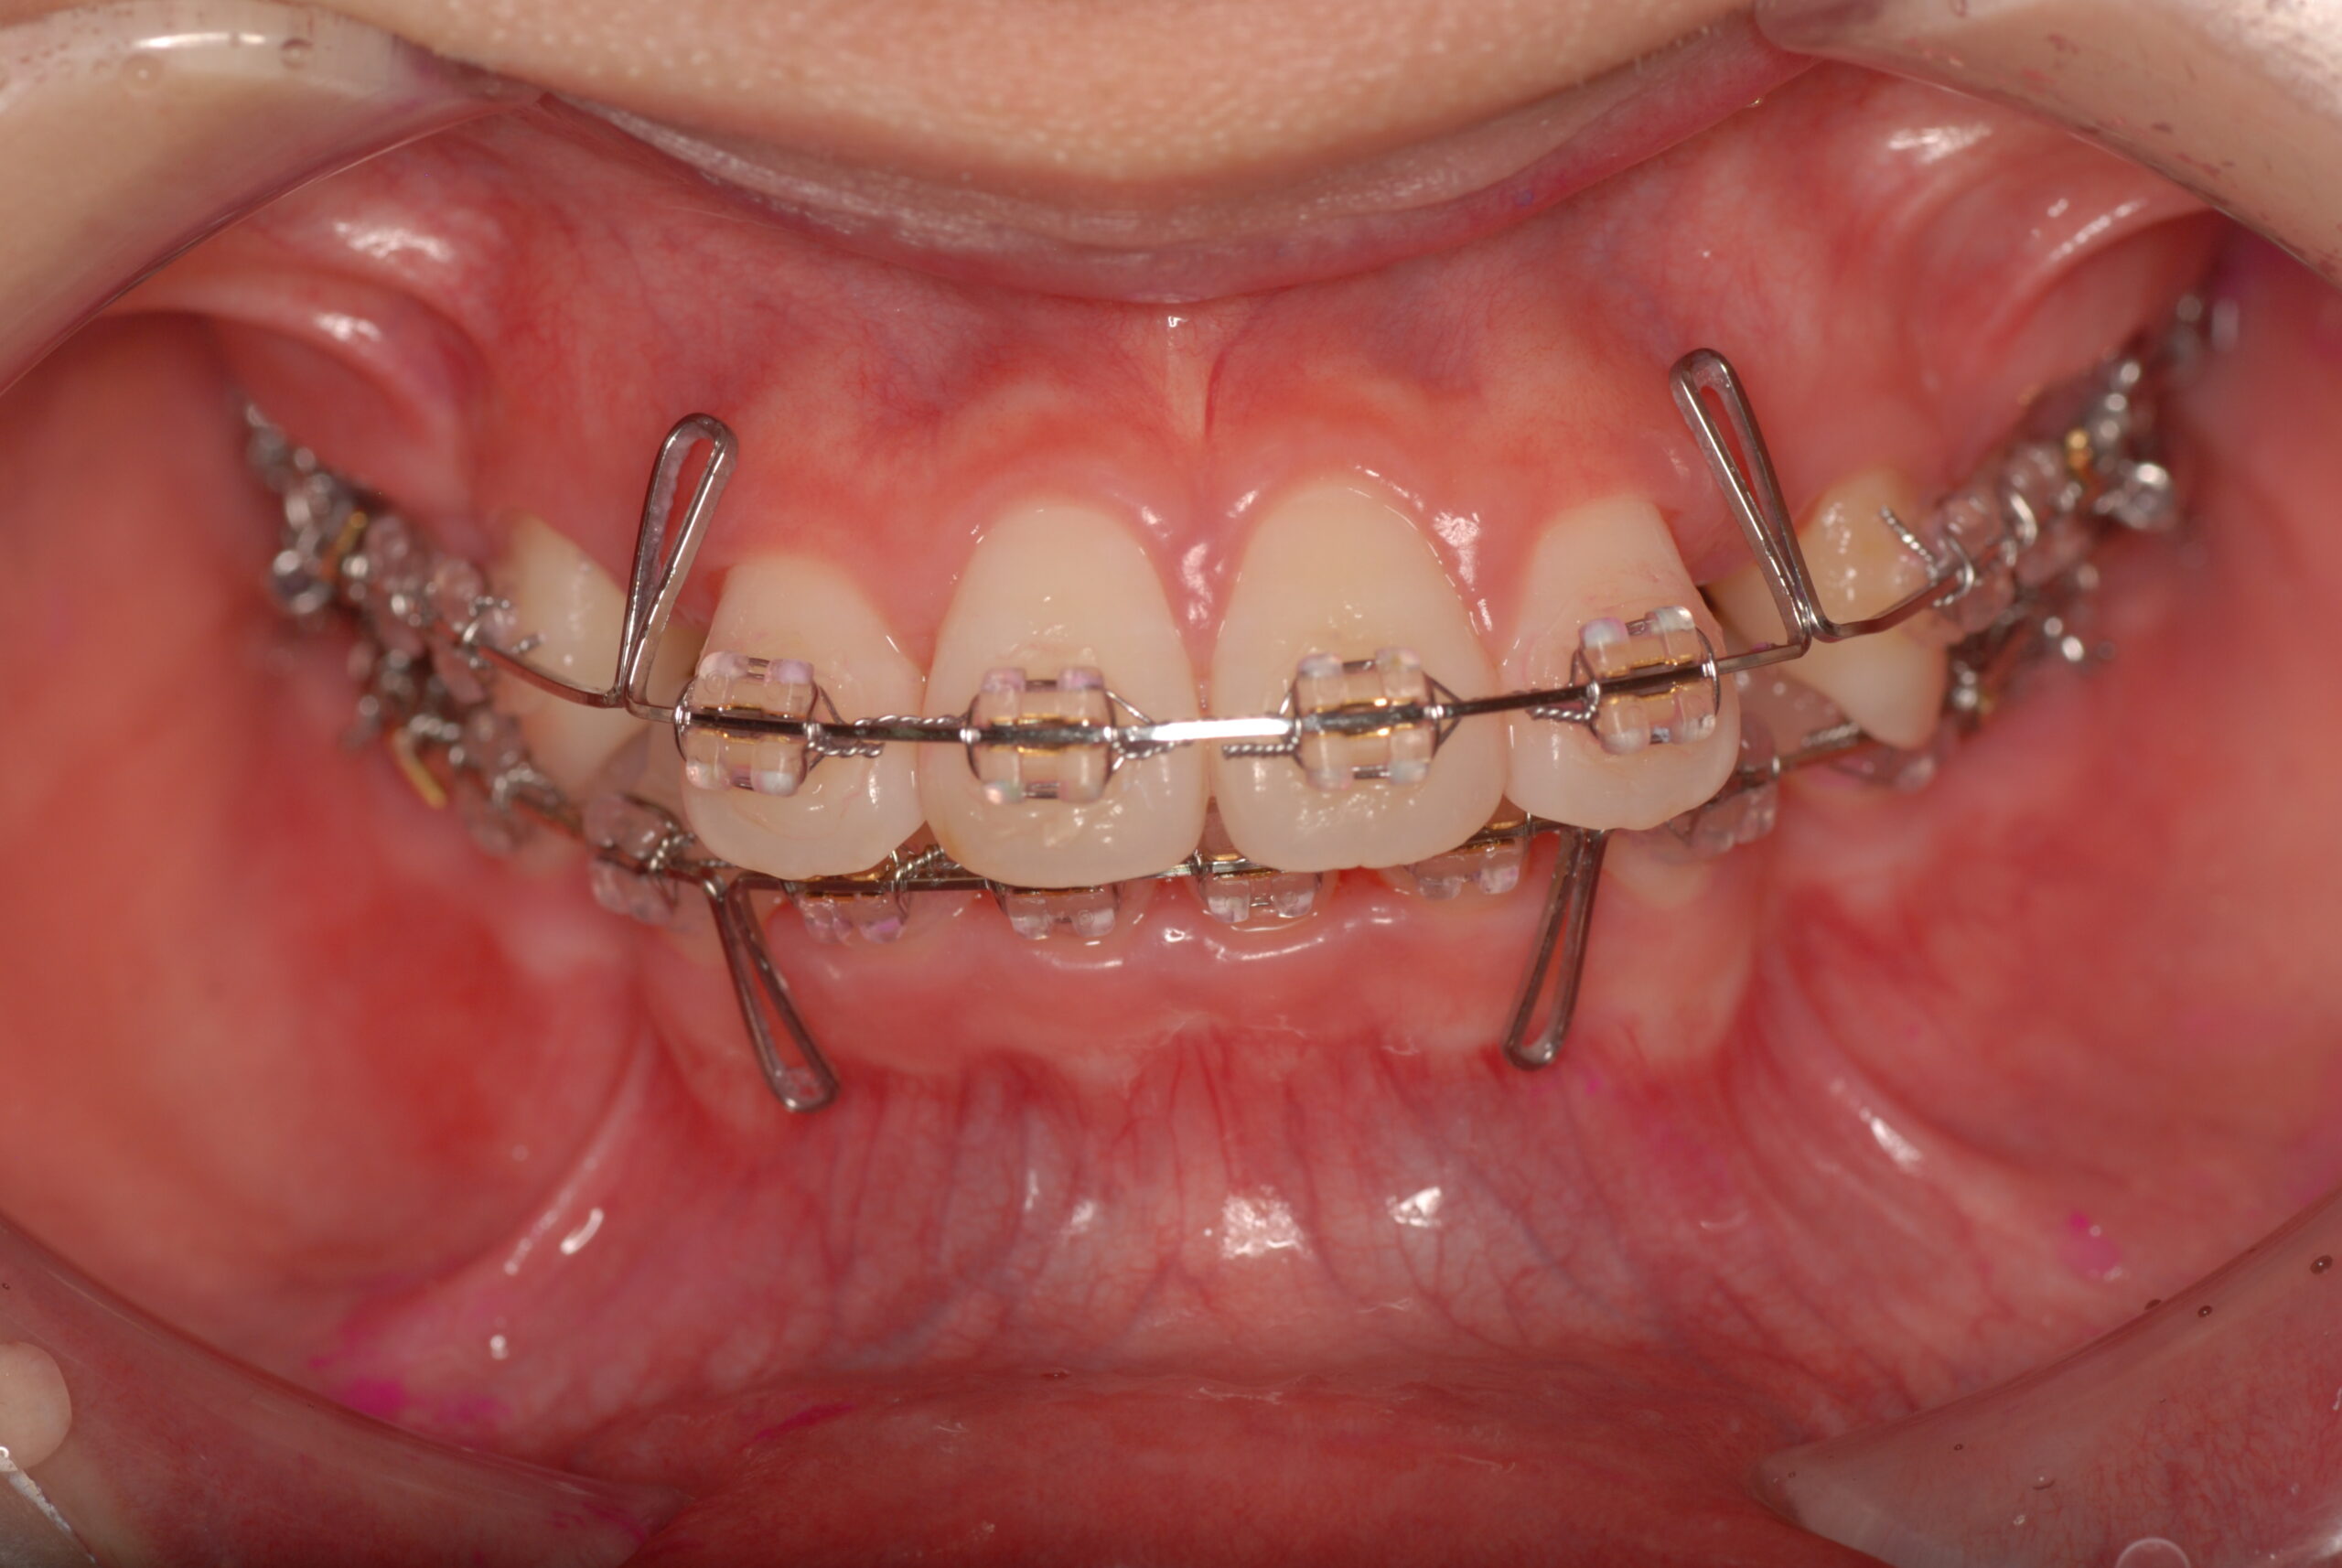

Progress

- 上顎前突、叢生。 上下顎第一小臼歯を抜歯し、抜歯空隙を利用し、顎外固定装置としてヘッドギヤを併用しながら、上顎前歯を可及的に後退させる。

- 約3年6か月 約90万円+消費税(検査診断料、矯正料、ヘッドギヤ代、月1回の処置料の総額)

- カリエス、歯肉炎、上顎前歯部後退の伴う歯根吸収、歯髄壊死、痛み